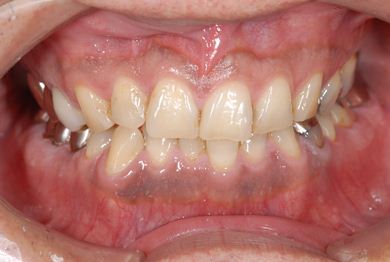

インプラントの症例写真 IMPLANT

インプラント治療+セラミック治療+歯肉歯槽骨整形術

| 性別/年齢 | 男性 / 47歳 | ||||||||||||||||||||||||||||||||

| 主訴 | 悪いところの治療と、歯をきれいにしたい。 | ||||||||||||||||||||||||||||||||

| 治療方針 | 右下奥、保存不能な歯を抜歯し、インプラント治療にて、機能的・審美的回復を行う。 | ||||||||||||||||||||||||||||||||

| 治療内容 | インプラント2本、メタルボンドセラミッククラウン9本(メタルボンド用土台6本)、ハイブリッドセラミッククラウン2本(セラミック用土台2本)、ハイブリッドセラミックインレー5本、歯肉歯槽骨整形術 | ||||||||||||||||||||||||||||||||